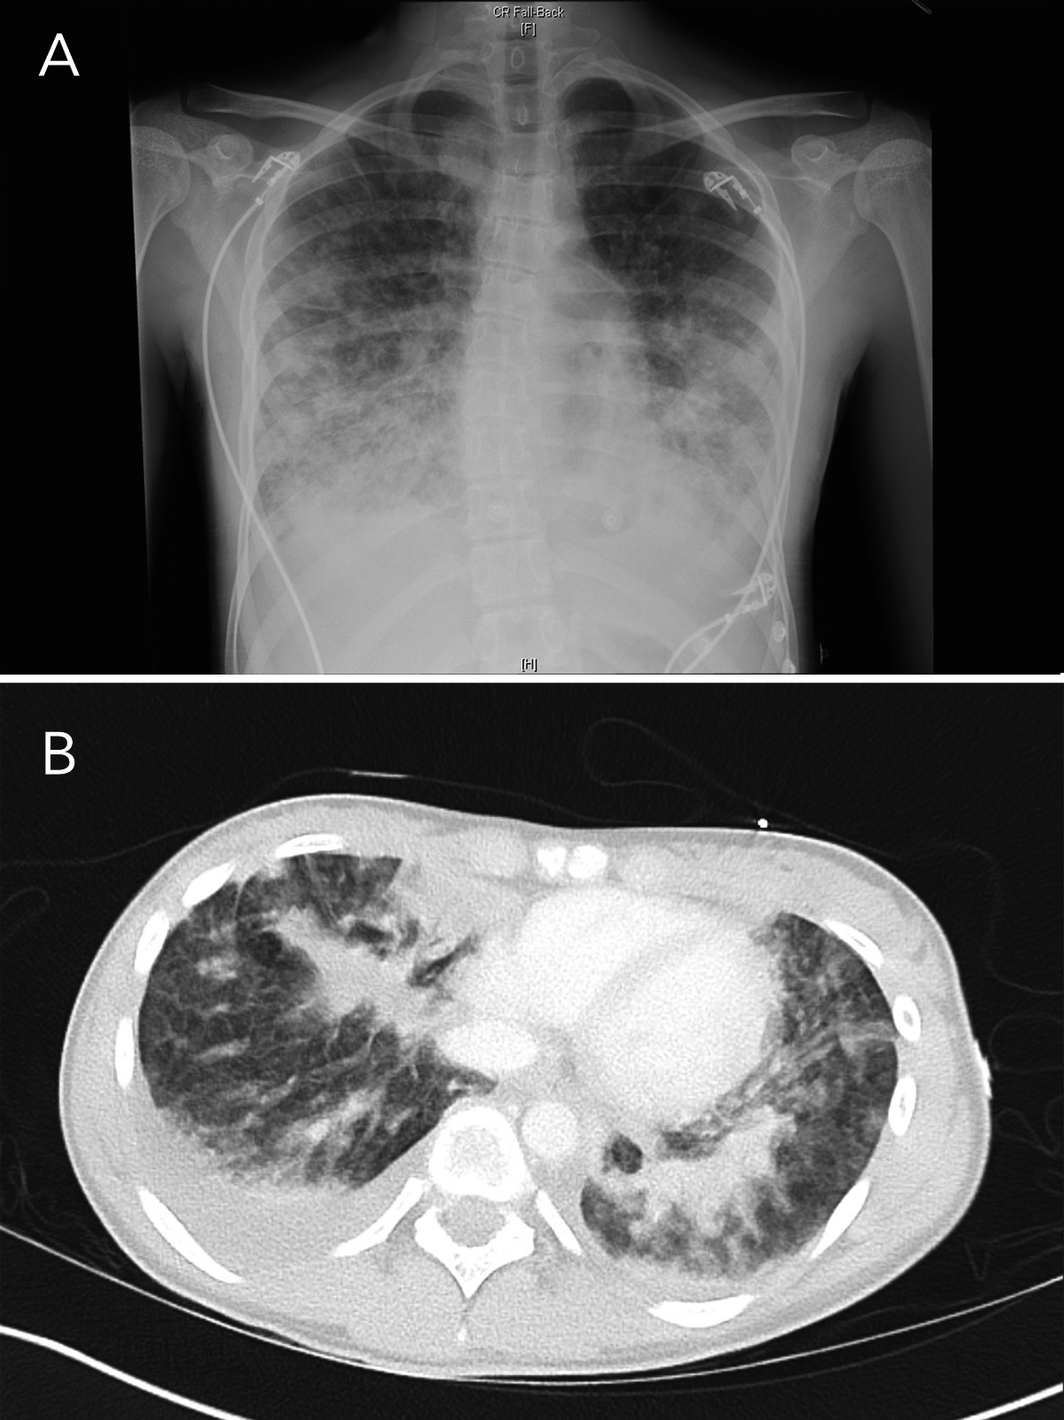

In September 2020, a Sydney public health unit was notified of the admission to a tertiary paediatric hospital intensive care unit of a 15‐year‐old girl with suspected e‐cigarette or vaping product use‐associated lung injury (EVALI), a pulmonary syndrome first reported in the United States.1 The girl had presented to another Sydney hospital with a 4‐day history of dysuria, urinary frequency and back pain followed by 2 days of vomiting and rigors. She was initially treated for urosepsis with intravenous antibiotics. She reported vaping nicotine two to three times weekly for the previous 7 months. She was febrile at 38°C, with a heart rate of 120–140 beats per minute, blood pressure of 110/80 mmHg, respiratory rate of 20 breaths per minute, and oxygen saturation of 92–95% on room air. A chest x‐ray showed bilateral pulmonary infiltrates that were worse in the lower zones (Box 1). Within hours, she became hypoxic, with oxygen saturation of 87% on room air. Abdominal computed tomography showed no abdominal pathology, but there were extensive pulmonary infiltrates in the lung bases with bilateral effusions (Box 1). Her urine drug screen result on the day of admission was positive for cannabinoids and benzodiazepines.

Box 1 – Chest x‐ray (A) and base of lung computed tomography (B) on first day of hospital admission, showing increased insterstitial opacities bilaterally, with areas of airspace opacities in the lower zones